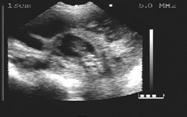

17 days of gestation

18 days of gestation